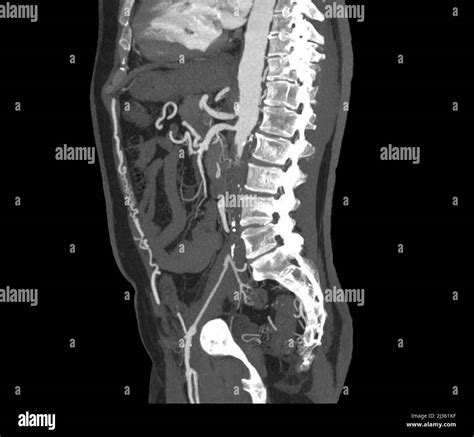

CTA / MRA Anatomic mapping Provides detailed 3D images of the aorta and iliac bifurcations.

Catheter Angiography Invasive gold standard Used primarily during intervention to visualize flow while treating the blockage.